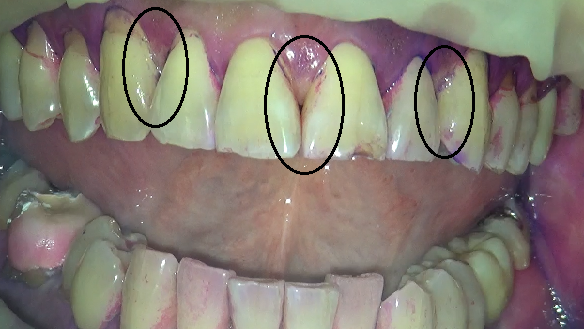

三か所、ピンポイントで磨いてみましたが、

状況にあった道具を使うと簡単にプラークは落とす事が出来ます。

患者さんとも一緒に確認をして、歯間ブラシとタフトブラシの再開をお願いしました。